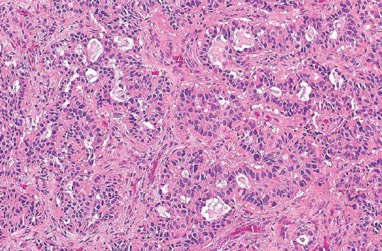

1058. На микрофотографии

изображена опухоль среднего уха, удаленная у 40-летнего пациента, страдавшего от кондуктивной тугоухости, диагноз _____ более вероятен